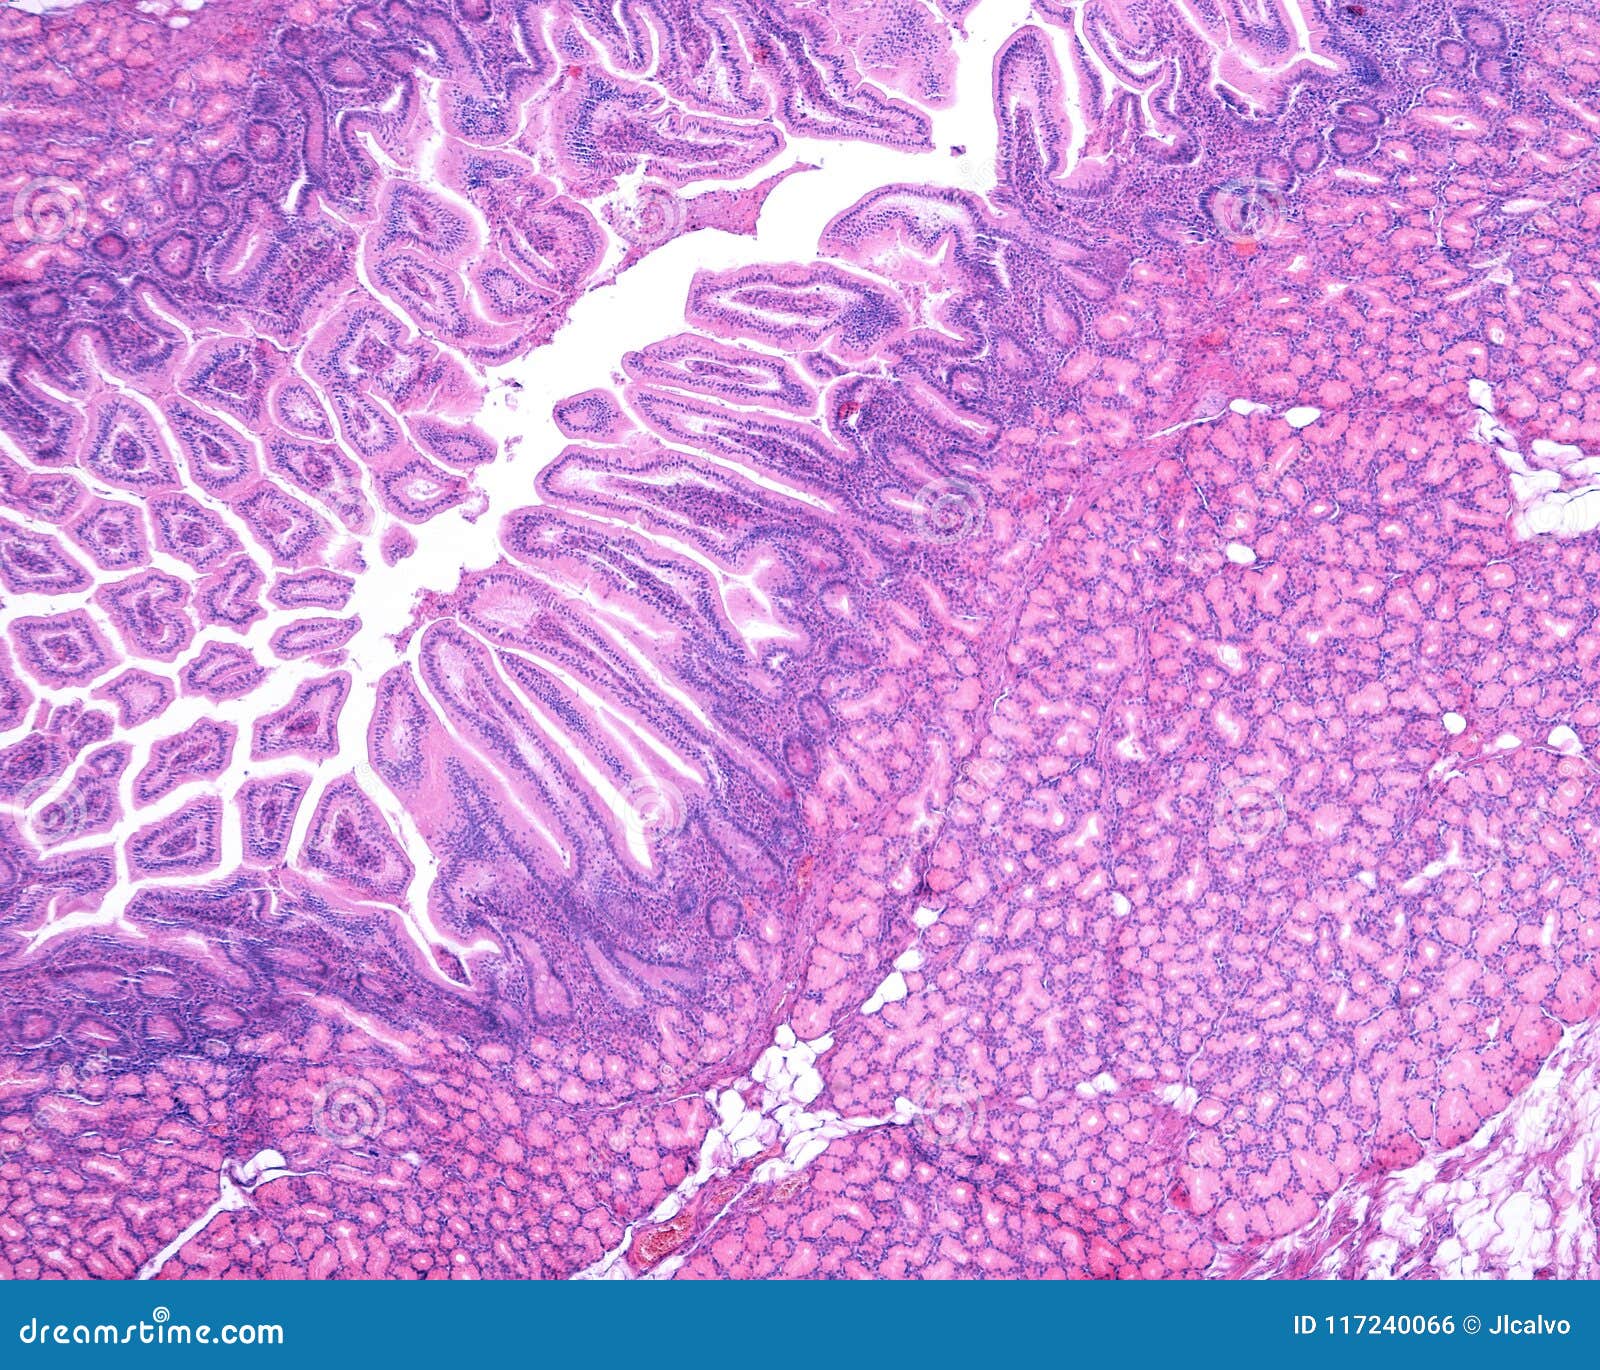

Light micrograph of a pylorus from a human stomach. At top is the Brunner's Glands In Pylorus Brunner's gland hamartoma arising from the pyloric ring. Brunner's gland adenomas have also been reported in the stomach, the pylorus, jejunum, and the head of the pancreas. Brunner's gland hamartomas (bghs) are uncommon lesions of duodenum which show hyperplasia of these glands along with smooth muscle bundles, adipose tissue and lymphoid. Learn about their histology, clinical. Brunner's glands are mucous. Brunner's Glands In Pylorus.

Pylorus. Transition between the gastric mucosa of the pyloric antrum Brunner's Glands In Pylorus Brunner's gland hamartomas (bghs) are uncommon lesions of duodenum which show hyperplasia of these glands along with smooth muscle bundles, adipose tissue and lymphoid. Brunner's gland hamartoma arising from the pyloric ring. Brunner's glands are mucous glands in the duodenum that produce alkaline secretion to protect the intestine from acid and activate. Learn about their histology, clinical. Brunner's gland adenomas. Brunner's Glands In Pylorus.